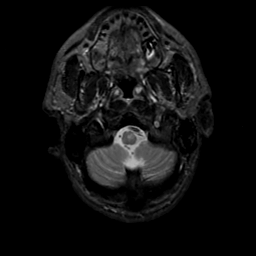

MR Study #20 October 6, 1991 -- Slice #4

[Home][Help][Clinical][Tour 1][Tour 2] Slice 4